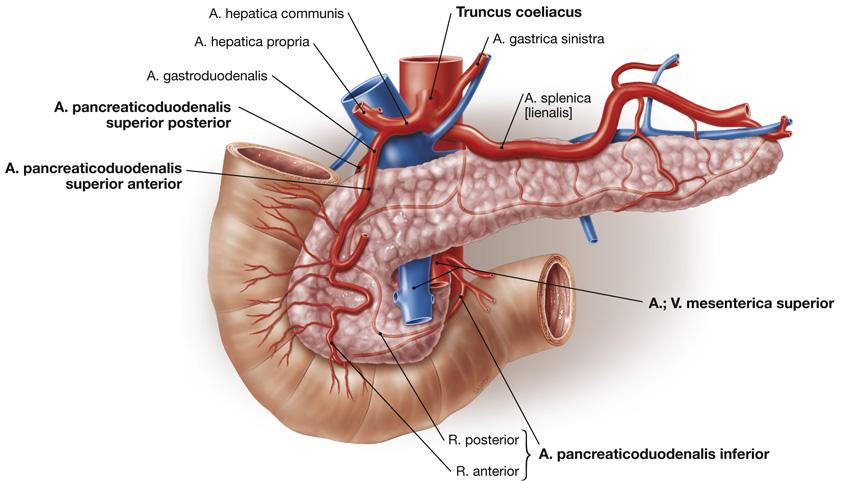

Fig 3.22: tr. coeliacus

diaphragma (groen) oesophagus -

ventriculus = maag

duodenum milt -

aorta abdominalis

|

|

Fig 3.23: a. mesenterica superior (AMS)

|

|